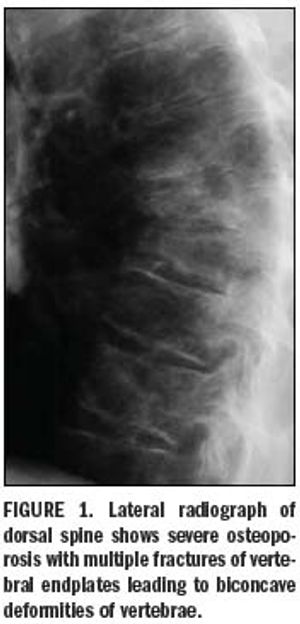

Imaging tools transform diagnosis of osteoporosis

Bone mineral density measurements of the axial and appendicular skeleton are an important part of the diagnosis and follow-up of metabolic bone disease.